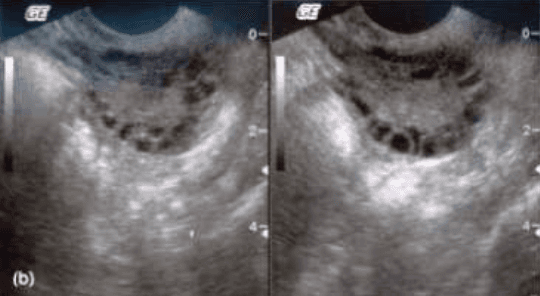

What are polycystic ovaries?

Polycystic ovaries have several features which include many growth-arrested follicles, thickened ovarian capsule (tunica albuginea) and an more amount of ovarian cortex with increase collagen content, having a more fibrous composition.